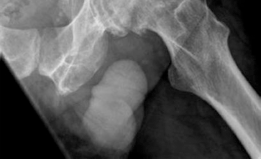

A standard radiographic series of the right hip was obtained, including an anteroposterior pelvis, a cross-table lateral, and a Dunn lateral view.

The anteroposterior pelvis radiograph demonstrated severe, end-stage osteoarthritis of the right hip. Findings included complete obliteration of the superolateral joint space, extensive subchondral sclerosis, and large osteophyte formation at both the acetabular rim and the femoral head-neck junction. Subchondral cystic changes were evident in both the acetabular dome and the weight-bearing portion of the femoral head. The Tönnis grade was classified as Grade 3.